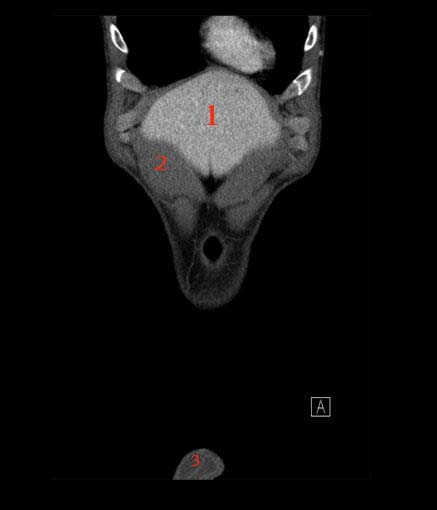

Abdomen coronal IQ test